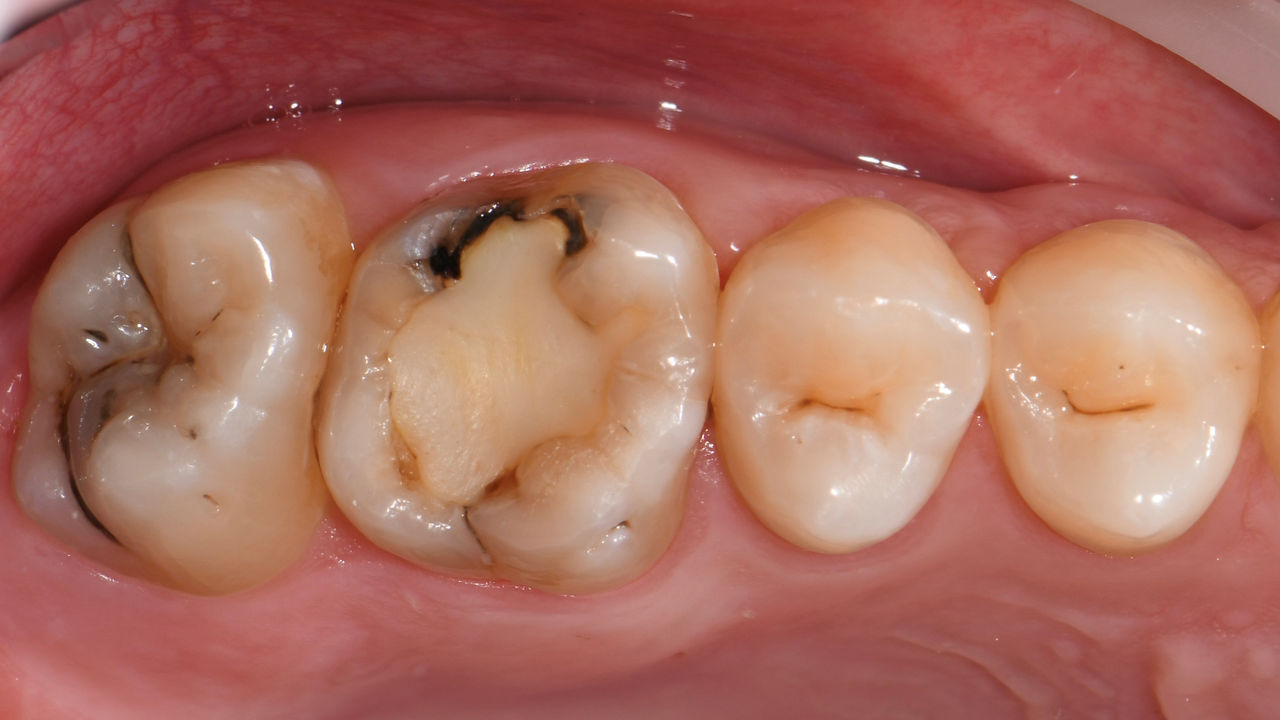

Avant : Restauration en amalgame défaillante nécessitant un remplacement. Patient se plaignant de sensibilité et dent présentant de multiples fissures.

Après : Restauration d’une couronne partielle CFAO réalisée en consultation avec la vitrocéramique CEREC Tessera Advanced Lithium-Disilicate.